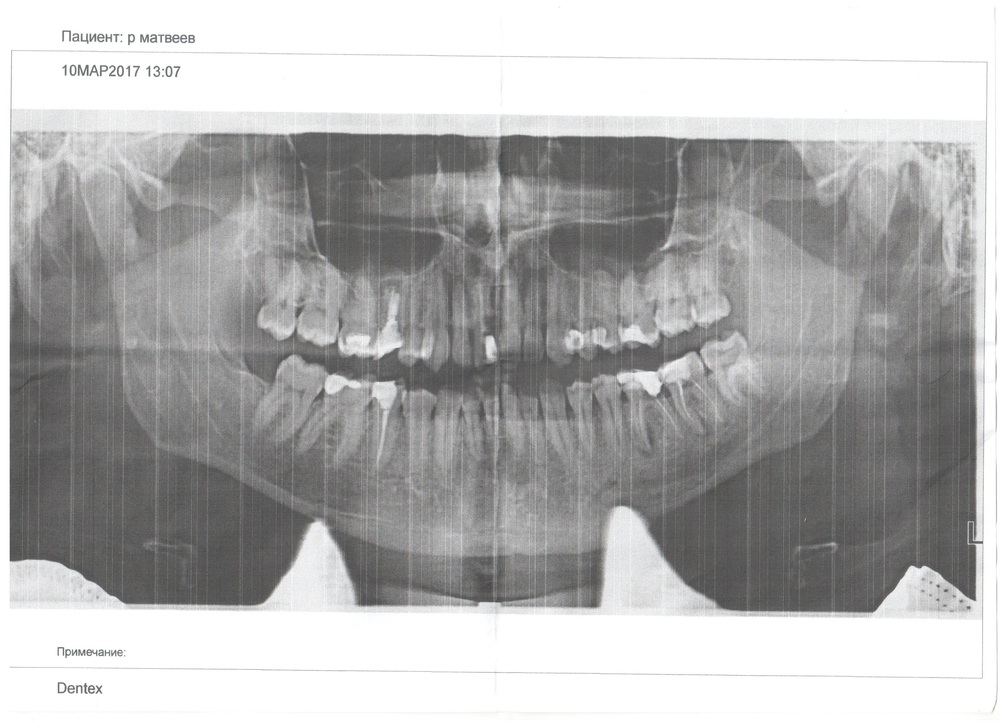

Пульпит зуба — это воспалительный процесс, затрагивающий мягкие ткани, расположенные в зубной полости, и вызывающий приступы острой боли, усиливающиеся в ночное время. Воспаление пульпы, или иными словами нерва, чаще всего возникает из-за попадания в мягкие ткани зуба болезнетворных микроорганизмов. Путь проникновения микробов в пульпу — поврежденная зубная эмаль. Причиной повреждения могут стать осложнения от кариеса, вызванные отсутствием своевременного лечения, механические повреждения (скол, перелом, травма), а также некачественные материалы, использованные при пломбировании. На рентгенограммах чаще всего это выглядит вот так:

Ну... или как-то так...

Дело в том, что пульпа является мягкой тканью, а рентгеновские лучи задерживаются только в твердых, в результате чего и получается изображение. Таким образом, на снимке может отразиться только изменение костной ткани: кариозная полость, деформация эмали, гранулема или радикулярная киста. Следовательно, как выглядит пульпит на снимке? Да точно так же, как и здоровый зуб. Единственным исключением является гангреозный тип воспаления, когда отмирание мягких тканей сопровождается выбросом токсичных веществ за верхнюю часть зубного корня, что провоцирует медленное рассасывание костной ткани. Плотность кости уменьшается и это отражается на рентгеновском снимке.

Исходя из вышесказанного, увидеть пульпит на снимке невозможно. То есть различить, что беспокоит пациента, пульпит или кариес, можно только вскрыв зубную эмаль и удалив поврежденную ткань. Однако это вовсе не значит, что рентген будет абсолютно бесполезен, ведь он поможет выявить отсутствие сопутствующих проблем.